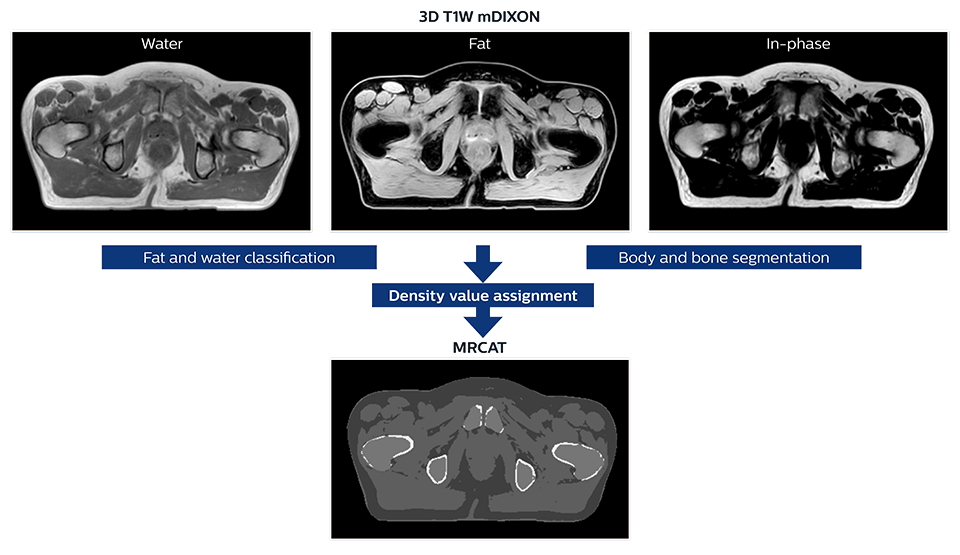

MR-only simulation workflow The 3D T1W FFE mDIXON sequence provides in-phase, water and fat images in one acquisition. Target and organs-at-risk are delineated on the 3D T2W TSE images. Prostate GTV is shown in orange, PTV in purple. The 3D bFFE sequence is used by the planner to mark the position of the fiducial markers (gold anchors) and contours are transferred to the digitally reconstructed radiographs (DRRs).

Based on the 3D T1W mDIXON images, MR-based density maps (MRCAT) are automatically generated. The VMAT (Volumetric Modulated Arc Therapy) plan is generated in TPS, based on MRCAT as primary image set. During the commissioning phase, dosimetric agreement between MRCAT-based and CT-based dose plans was studied and differences in the PTV dose were found to be minimal (<1% for most patients). Average difference in PTV mean values was 0.8% over the study group (n=62).

The Philips MRCAT approach for an MR-only based dose planning provides CT-like density information calculated from MR images for dose calculations, as well as high contrast anatomical T2W images for target delineation. [2-3] The MRCAT images with density information are DICOM conform and can be automatically exported to treatment planning systems (TPS) as primary image dataset for dose calculations and to generate MR-based digitally reconstructed radiographs (DRRs).

Electron density information is automatically generated on the MR console from a single T1W mDIXON MRI sequence in two steps: